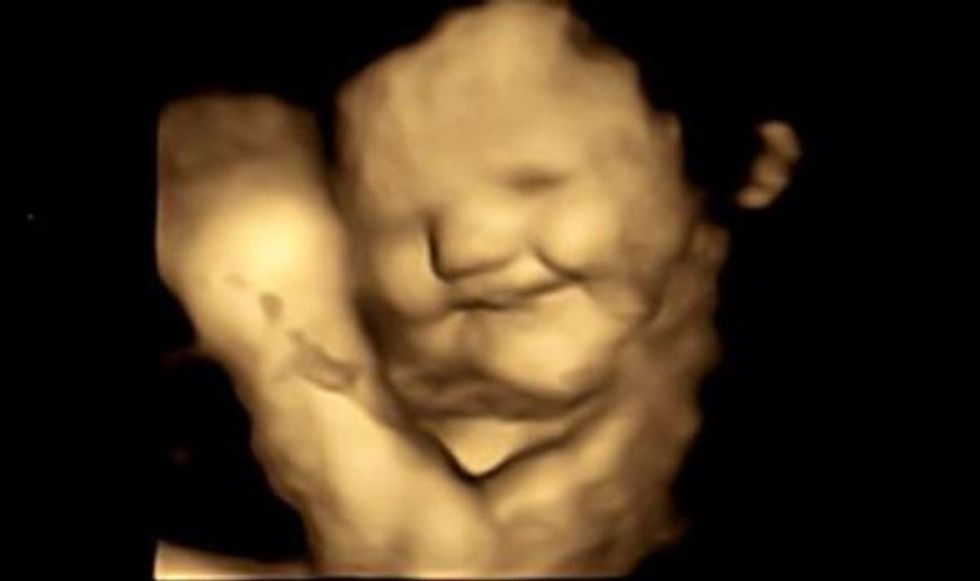

Skanimet e 100 nënave të ardhshme tregojnë fetuset që japin më shumë përgjigje "të qeshura" ndaj karotave, por reagime "të qara" ndaj lakrës së gjelbër.

Mendohet se fetuset përjetojnë shije duke thithur dhe gëlltitur lëngun amniotik të mitrës. Ekspertët regjistruan reagime menjëherë pasi nënat morën kapsula me shije karote dhe lakre të gjelbër.

Reagimet e fytyrës të parë në të dy grupet e shijes treguan se ekspozimi ndaj vetëm një sasie të vogël të shijes së karotës ose lakrës së gjelbër stimuloi një përgjigje. Bashkautorja e hulumtimit, Profesor Jackie Blissett, nga Universiteti Aston, Birmingham, tha: “Hapi tjetër është të ekzaminohet nëse fetuset tregojnë më pak përgjigje 'negative' ndaj këtyre shijeve me kalimin e kohës, duke rezultuar në pranim më të madh kur foshnjat i shijojnë ato për herë të parë jashtë mitrës”.